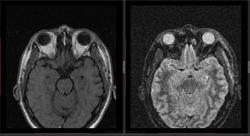

- https://radiomed.ru/sites/default/files/styles/case_slider_image/public/user/16807/2_41.jpg?itok=Phr_eCUu

- https://radiomed.ru/sites/default/files/styles/case_slider_image/public/user/16807/8_3.jpg?itok=_0vgWjN6

дифференциальная диагностика ganglion ,нодулярный фасциит,нейрофиброма,дерматофиброма